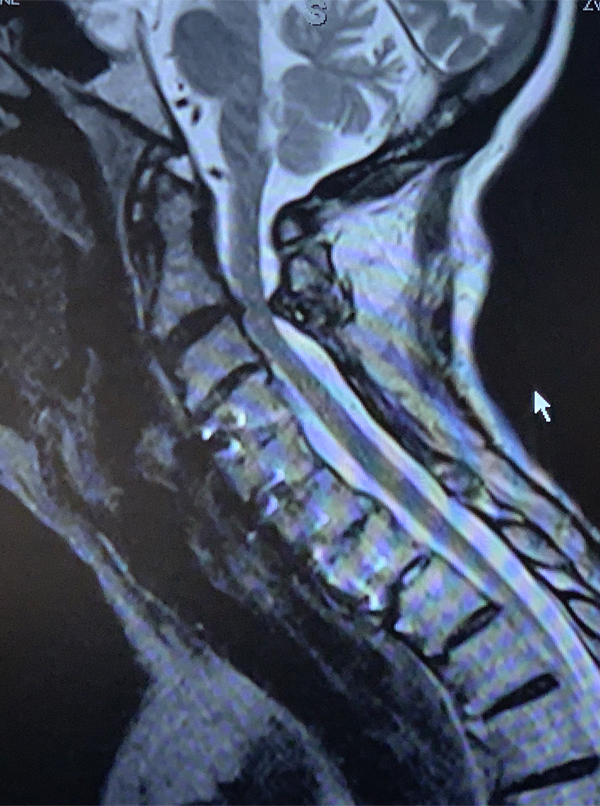

An MRI (Fig. 1) demonstrated severe stenosis at C2-3 with cord compression secondary to significant thickened posterior ligament and facet arthropathy. The patient had a posterior cervical laminectomy C1-3 to decompress the spinal cord and instrumented fusion C2-4.On exploration, the patient was deemed to be fused and the previous hardware was removed except for the lateral mass screws at C3 and C4 were left in. Postoperatively the patient had an uneventful course with some improvement in finger extensor strength.

Figures 2a, b, c: Preoperative sagittal CT scans of the cervical spine demonstrating preoperative instrumentation. Note degenerative changes and anteriolisthesis of C2 and C3.